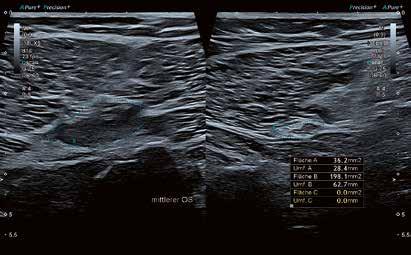

Hochauflösender Ultraschall in der Sportpraxis

Wie kamen Sie zur Sonographie?

„Ultraschallsysteme am Bewegungsapparat und am Herzen haben mich die letzten 20 Jahre sehr intensiv begleitet. Ich habe 2001 meine herz- und gefäßchirurgische Facharztausbildung bei Prof. Haverich an der Med. Hochschule Hannover begonnen, wo ich bereits mit den Duplexverfahren die Carotiden und auch die Beinarterien prüfte. Eines meiner Forschungsprojekte war beginnend 2002 die Mikrozirkulation, die ich mit einem kombinierten Laser-Doppler- und Spektrophotometriesystem, dem Oxygento-see von LEA Medizintechnik, untersuchte – zunächst in der Herzchirurgie die Brustwanddurchblutung nach IMAEntnahme bei der Bypass-Operation und später die Handperfusion nach Radialisentnahme als arteriellem Graft.

Nach meinem Wechsel 2004 in die Unfallchirurgie habe ich z. B. mit einem portablen australischen Ultraschallsystem (USCOM) als Hubschraubernotarzt am Notfallort Hämodynamikmessungen mit Bestimmung des Herzzeitvolumens durchgeführt.

Das vorgenannte Oxygen-to-see-System habe ich dann an Achillessehnen eingesetzt und entdeckte 2005 einen gesteigerten Blutfluss bei midportion-Achillodynie, was im American Journal of Sports Medicine seinen Platz fand.“

Welche Systeme haben Sie begleitet?

„Für die klinische Sonographie am Bewegungsapparat habe ich in der MHH ein Toshiba System eingesetzt, bei dem ich einen hervorragenden Power-Doppler-Modus vorfand, um die Neogefäße an entzündeten Sehnen zu visualisieren. Ich habe 2005 begonnen, Power-Doppler-gesteuerte Sklerosierungen dieser Neogefäße mit Polidocanol vorzunehmen. Daher habe ich mich zu Beginn meiner Sportpraxis 2012 aufgrund der Power-Doppler-Sonographie für ein Toshiba Nemio System mit einem Linearschallkopf und einer Hockeysticksonde für die Handchirurgie entschieden. Dieses habe ich auch für die dynamische Sonographie von A1-Ringbandstenosen mit großem Gewinn eingesetzt.“

INTERVIEW // ULTRASCHALL // Aplio i800

Prof. Dr. Karsten Knobloch aus Hannover

56 // VISIONS 31

Warum haben Sie sich jetzt für ein Highend-Ultraschallsystem entschieden?

„2017 habe ich zum ersten Mal in einer Teststellung den weiterentwickelten Superb Micro Vascular Imaging (SMI) Modus getestet und war schon begeistert. Ich wollte aber zusätzlich eine verlässliche und einsetzbare quantitative Scherwellenelastographie, wie sie jetzt im Aplio i800 System zu finden ist. Außerdem sind die Matrixschallköpfe bis 33 MHz für mich von immenser Bedeutung.“

Wer sind Ihre Patienten in der Sportpraxis?

„Der typische Patient in meiner Sportpraxis ist männlich (in 70 % der Fälle), im mittleren Alter von 52 Jahren und stellt sich mit einem Achillessehnenproblem vor. Er ist Hobbyläufer oder Fußballer oder Tennisspieler und sucht mich häufig für eine Zweit-, Dritt- oder Viertmeinung zur gezielten Diagnostik und Therapie der Achillessehnenbeschwerden auf.“

Sie bieten in Ihrer Praxis Spitzendiagnostik für Sportler aus ganz Deutschland an. Was sind die häufigsten diagnostischen Fragestellungen für den Ultraschall?

„Für gewöhnlich suchen mich Patienten mit Sehnenproblemen auf, vornehmlich der Achillessehne, der Patellasehne, der plantaren Faszie am Fuß, aber auch weiterer Sehnen an der unteren Extremität wie der Quadricepssehne oder der Peronealsehnen. An der oberen Extremität sind die Supraspinatussehne und die lange Bizepssehne an der Schulter, die gemeinsame Extensorensehne am lateralen Ellenbogen, die Flexor-carpi-ulnaris-Sehne beim Golferellenbogen und die Handsehnen streck- wie beugeseitig schmerzhaft. Nach der eingehenden Anamnese und der klinischen Untersuchung inklusive Funktions- und z. T. Krafttests führe ich dann eine umfassende Ultraschalluntersuchung unter Einsatz der Graustufensonographie, der unterschiedlichen Dopplermethoden und neuerdings auch der Scherwellenelastographie durch.“

Welchen Stellenwert hat die Hochfrequenzsonographie in Ihrer Praxis?

„Bei jedem von mir sonographierten Patienten setze ich die Power-Doppler-Sonographie und den SMI-Modus zur präzisen Beurteilung der Mikrogefäßarchitektur ein. Die PowerDoppler-kontrollierte Injektionstherapie bei Tendinopathien –sei es mit Polidocanol zur Sklerosierungsinjektion oder der Hyaluronsäure Ostenil Tendon – ist eine ganz wesentliche Therapieoption für Tendinopathien an der oberen und unteren Extremität in meiner Sportpraxis.“

Beeinflusst die neue Technik Ihre therapeutische Vorgehensweise?

„Ja, durch das SMI in Ergänzung zur Power-Doppler-Sonographie kann ich noch präziser die Neovaskularisation visualisieren, wobei ich mir zunächst in SMI colour, dann auch im SMI-monochrome-Modus – ähnlich einer in-vivoMikroskopie – ein genaues Mikrogefäßbild mache.“

VISIONS 31 // 57 © 2021 C ANON MEDICAL SYSTEM S

„Bei jedem von mir sonographierten Patienten setze ich die Power-DopplerSonographie und den SMI-Modus zur präzisen Beurteilung der Mikrogefäßarchitektur ein.“

Welchen Nutzen haben Ihre Patienten davon?

„Je präziser und quantitativer die Diagnose, desto besser lässt sich einerseits der Schweregrad beispielsweise einer Achillodynie einschätzen und umso besser können prognostische Einschätzungen und therapeutische Empfehlungen gegeben werden.“

Wie bewerten Sie die neuen Möglichkeiten der quantitativen Beurteilung der Gewebeelastizität für den Bewegungsapparat?

„Für mich ist die quantitative Scherwellenelastographie, die es mir nichtinvasiv ermöglicht, eine Aussage über die Gewebehärte zu generieren, offen gesagt eine Offenbarung. Ich lerne mit jedem untersuchten Patienten die Elastizität der untersuchten Sehne in m/s besser kennen und beobachte auch den Einfluss meiner therapeutischen Bemühungen mit den unterschiedlichen von mir eingesetzten Techniken.“

Eröffnung der SPORTPRAXIS am 1. Dezember 2012. Im Bild: Prof. Knobloch mit Philipp Bargfrede, SV Werder Bremen. Kevin DeBruyne, derzeit Manchester City.

58 // VISIONS 31

Alex Meier, ehemals Eintracht Frankfurt, jetzt U16-Trainer Eintracht Frankfurt.

In puncto Bildgebung und Diagnostik sind Sie sehr innovativ unterwegs. Welche Entwicklungen wünschen Sie sich in naher Zukunft für den Ultraschall?

„Ich darf kurz ergänzen – auch in der Therapie bin ich sehr innovativ, setze nichtinvasive Techniken wie die fokussierte und radiale Stoßwellentherapie, die Low Level Lasertherapie, neuerdings auch die ultraschallgestützte galvanische Elektrolyse (Gymna Acure 8000) wie auch die extrakorporale Magnetotransduktion (EMTT) mit dem Magnetolithsystem ein. Von der Sonographie erhoffe ich mir in der Zukunft u. a. eine Fusion mit Schichtbildverfahren, insbesondere mit der Cone Beam CT, die ich als DVT in meiner Praxis für die Knochenbildgebung einsetze. Des Weiteren erhoffe ich mir weitere Verbesserungen in der Scherwellenelastographie oberflächennah <1 cm, wo mitunter Grenzen in der Erfassung der Scherwelle auftauchen. //

Spindelförmig verdickte midportion Achillestendinopathie auf 10,6 mm ap-Durchmesser vs. 6,8 mm auf der gesunden Gegenseite. Die Scherwellenelastographie zeigt die pathologische Elastizität mit 7,2 m/s (links) vs. 3,8 m/s (rechts).

„Für mich ist die quantitative Scherwellenelastographie, die es mir nichtinvasiv ermöglicht, eine Aussage über die Gewebehärte zu generieren, offen gesagt eine Offenbarung."

Prof. Dr. Karsten Knobloch, FACS

Prof. Knobloch 2005 als Notarzt im RTH Christoph 4 bei portabler Hämodynamikmessung mit dem USCOM-System.

M.

Osgood Schlatter, dargestellt mit SMI und Scherwellenelastographie. Nachweis der reduzierten Elastizität der distalen Patellasehne an der noch nicht vollständig verknöcherten Tuberositas tibiae.

VISIONS 31 // 59 © 2021 C ANON MEDICAL SYSTEM S

Ellenbogen eines Golfpatienten nach dreimonatiger Schmerzdauer. Darstellung der entzündeten M. flexor carpi ulnaris Sehne mit SMI. Die Sehne zeigt eine normale Elastizität.

Ein Plädoyer für hochwertige Ultraschallausrüstung in der neurologischen Praxis

Wenn Sie als Neurologe Besuch von Profi-Handwerkern bekommen, sind Sie in der Regel beeindruckt von deren Geräteausstattung mit meist High-End-Geräten namhafter deutscher oder Schweizer Hersteller.

Dagegen mutet ein Blick auf die Ultraschallausstattung in der eigenen Praxis oft ernüchternd an. Warum sind hier viele Kollegen so „sparsam“ unterwegs und ist das wirklich sinnvoll?

Bislang bestand die Anwendung des Ultraschalls in der neurologischen Praxis ausschließlich im vaskulären Ultraschall der hirnversorgenden Gefäße (also v. a. extra-/intrakranielle Doppler- und Duplexsonographie). Mit der Nerven- und Muskelsonographie hat sich in den letzten Jahren jedoch eine weitere Anwendungsmöglichkeit erschlossen, die insbesondere auch die Anschaffung qualitativ höherwertiger Geräte sinnvoll bzw. sogar nötig macht. Abgesehen davon, dass sich mit einer höherwertigen technischen Ausstattung natürlich auch bessere Befunde und damit für den Patienten bessere und ggf. wichtige diagnostische und therapeutische Entscheidungen treffen lassen, sprechen auch wirtschaftliche Aspekte eigentlich klar für den Einsatz von Premium-Ultraschallsystemen.

Beispiel für den vaskulären Ultraschall

Extrakraniell lässt sich in der Regel auch mit älteren und einfacheren Geräten zumindest die Carotisbifurkation zuverlässig darstellen. Schwieriger sind oftmals bereits die distalen Abschnitte der A. carotis oder die A. vertebralis (inkl. deren Abgängen) darstellbar, was zudem durch ungünstige anatomische Verhältnisse/eine ungünstige anatomische Konstitution des Patienten nochmals erschwert werden kann. Intrakraniell ist mit älteren oder einfacheren Geräten häufig kein adäquates Schallfenster zu finden oder sind die intrakraniellen Gefäße nur schwierig und im Rahmen einer langwierigen Suche unter Optimierung des dürftigen Schallfensters darstellbar. Teilweise ist auch gar keine Untersuchung möglich, die mit leistungsstärkeren Geräten ggf. doch noch gelingen würde.

Aufgrund eigener Erfahrungen/Versuche mit unterschiedlichen Geräteklassen ist eine Zeiteinsparung pro Untersuchung von mind. 1 min bei Verwendung höherwertiger Geräte absolut realistisch. Bei konservativer Annahme von 150 Untersuchungen pro Quartal würde sich somit eine jährliche Zeitersparnis von ca. 10 h ergeben. Bei einem Umsatz/Stunde von 200 bis 300 € wäre dies eine Ersparnis von mind. 2.000 €.

Unser Gespräch mit Dr. Axel Schramm aus der neurologischen Gemeinschaftspraxis in Fürth. Dr. Axel Schramm

INTERVIEW // ULTRASCHALL // NeuroPraxis Fürth 60 // VISIONS 31

Circulus arteriosus inkl. sehr guter Sicht auf den Hirnstamm. A. und V. vertebralis.